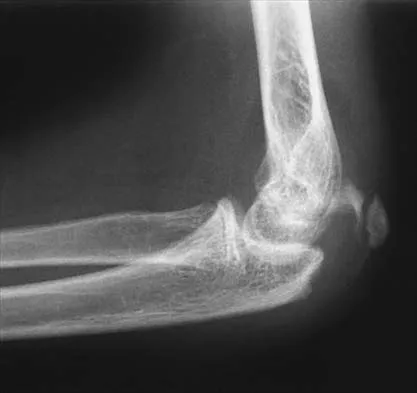

A 15-year-old boy falls from his bicycle and sustains an injury to his elbow. Prereduction radiographs are shown in Figure 12a. Closed reduction is performed without difficulty and postreduction radiographs are shown in Figure 12b. What is the next most appropriate step in treatment?

Explanation

Elbow dislocations in children are rare injuries and usually result from a fall on an outstretched arm. The incidence of these injuries increases as patients age and concurrently the incidence of supracondylar humerus fractures decreases. In adolescent patients, simple elbow dislocations are treated with splint immobilization and the initiation of physical therapy once comfortable. The practitioner must be aware of structures that may get caught in the joint on reduction. These include the median nerve as well as the medial epicondyle. In this patient, the radiographs reveal a medial epicondyle fracture. Postreduction radiographs show the joint to be incongruous secondary to intra-articular displacement. At this point, the most appropriate treatment is to perform an open reduction and repair of the medial epicondyle fragment. Rasool MN: Dislocations of the elbow in children. J Bone Joint Surg Br 2004;86:1050-1058.